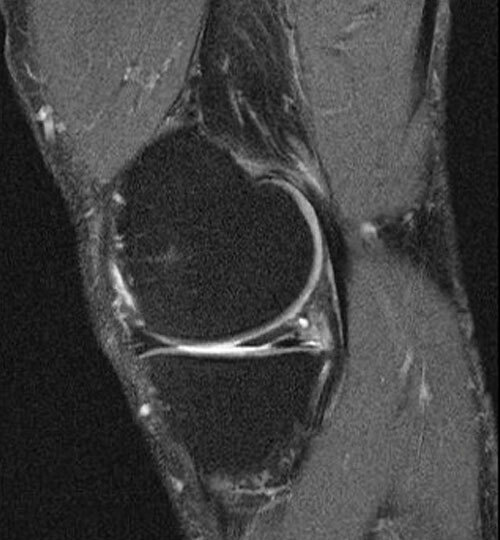

Soumis à d’importantes contraintes mécaniques, les ménisques — véritables amortisseurs du genou — peuvent se déchirer à la suite d’un traumatisme ou s’user avec l’âge (lésions dégénératives). Conduite à tenir, place de l’imagerie, options thérapeutiques selon les types de lésions, protocoles de rééducation et critères pour la reprise du sport… Tour d’horizon pour le MG.